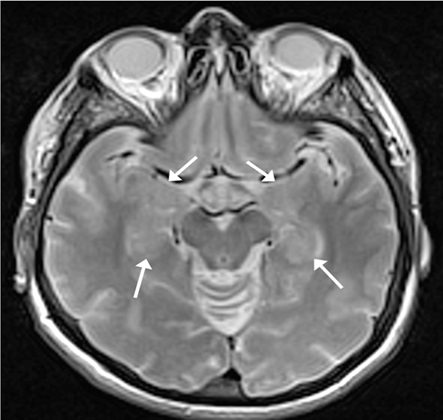

Ressonância nuclear magnética (RNM) cranioencefálica (ponderada em T2): demonstra hiperintensidade simétrica dos lobos temporais mediais bilaterais (hipocampos; destacada por setas apontando para o meio e a área anterior do hipocampo) consistente com a inflamação ativa em encefalite e encefalopatia límbicas. Hipocampos mais claros que as outras regiões de substância cinzenta, principalmente o córtex posterior

Do acervo pessoal do Dr. Geschwind, MD, PhD; usado com permissão